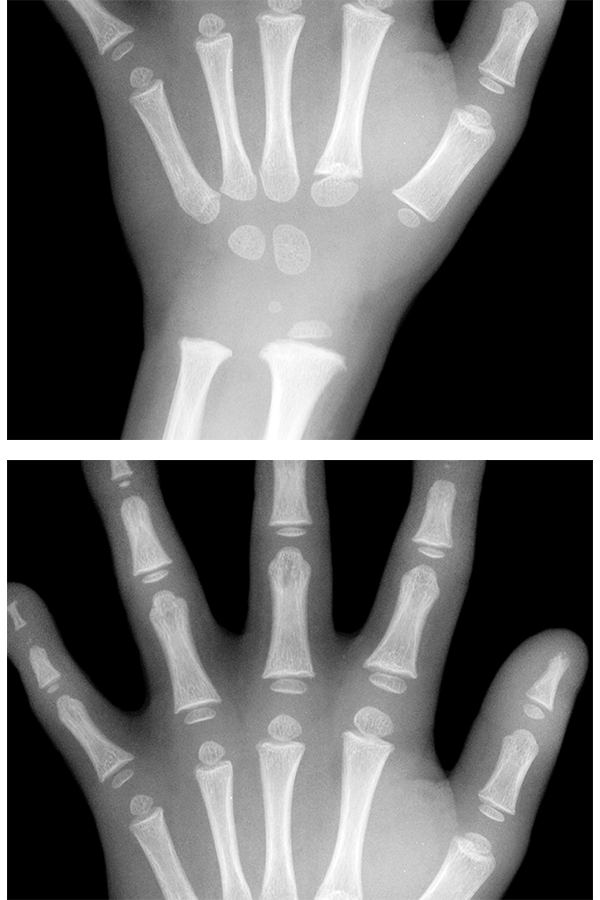

• [ 열린 성장판 ]

• [ 닫힌 성장판 ]

성장판, 골연령 검사 및

성장 예측키 분석

성장판 상태를 분석하여 아이의 뼈 나이를 측정, 현재 나이와 비교해 성장이 빠른지 늦은지 진단하며 어느정도 성장할 수 있는지 예상 할 수 있습니다.